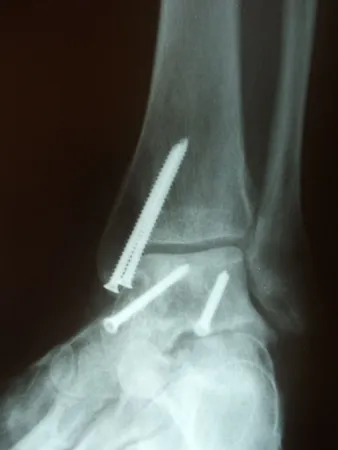

Pictures of a talar neck fracture with displacement of the talar body and subtalar and ankle dislocation prior to surgery